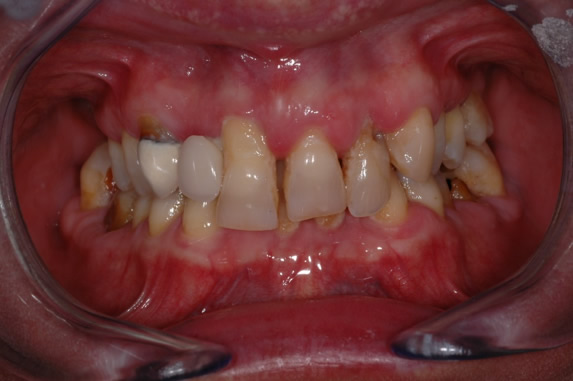

Fig.1 Caso clinico iniziale la paziente necessita di una riabilitazione implanto protesica superiore totale, si dovranno estrarre tutti i denti e consegnare nella stessa giornata un provvisorio fisso che abbia anche una estetica iniziale accettabile